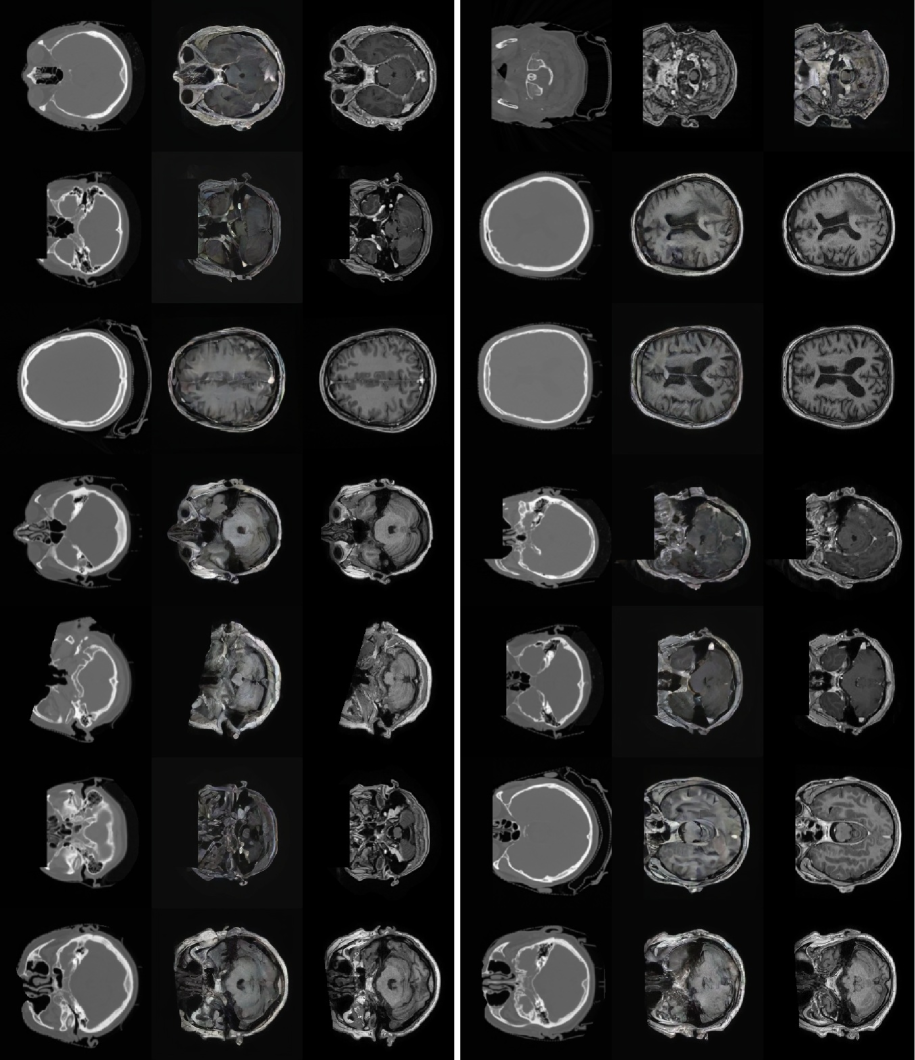

Refer to caption

Figure 5: Visualizations of 14 brain CT to MRI conversion pairs from the SynthRAD2023 dataset. Among each pair, Left is the inputed CT, Middle is the generated MRI and Right is the ground truth MRI. Zoom in for a better view.